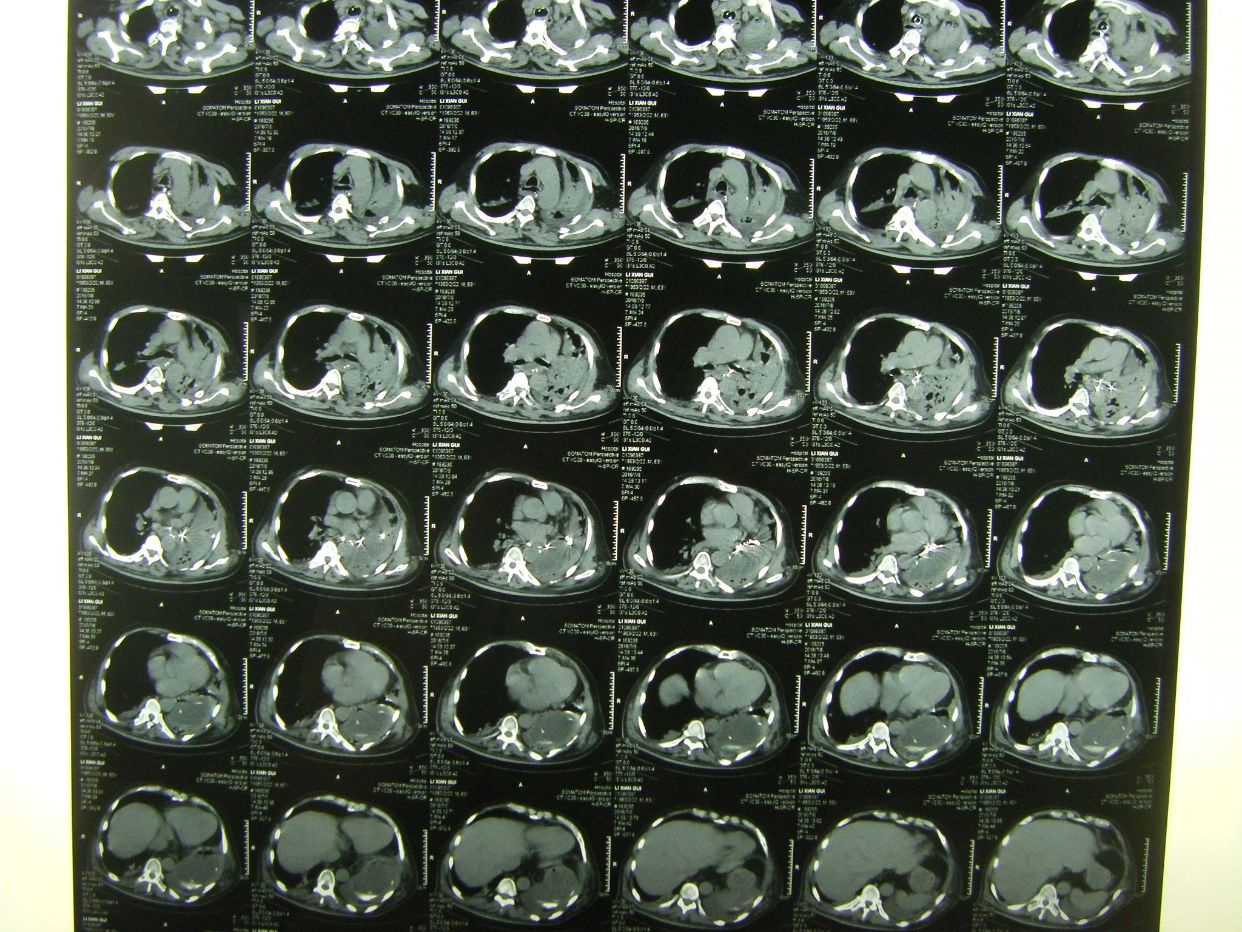

因呼吸急促,氧饱和度低,行胸部CT检查示,双肺野弥漫性斑片状阴影,保留气管插管,拍背吸痰,加强供氧,应用抗炎平喘化痰等药物治疗。

查血气分析示,丨型呼吸衰竭并呼碱,给予呼吸机辅助呼吸。

术后半月胸部CT复查示,肺部阴影消退。患者体温血象正常,神志清,遵嘱动作,右侧肢体肌力3级,出院康复。

术后8天,患者出现呼吸困难,氧饱和度下降,胸部CT示左侧肺野消失,考虑胃膈疝并肺不张肺感染。调整体位,拍背吸痰,应用呼吸机辅助呼吸等治疗。

胸部CT复查,肺不张恢复,肺部阴影消退。患者恢复意识,遵嘱动作,呼吸良好,体温血象正常,出院康复。